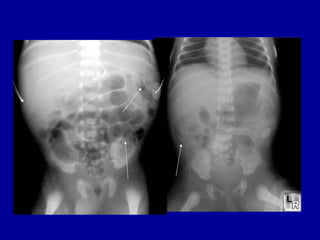

1.44 am

ORIGINAL REPORT • HISTORY • NEC, septic shock on CPAP, IA and IV lines. • REPORT • AXR - SUPINE AP • Compared with AXR taken 10 hours earlier. • The nasogastric tube is now seen projected over the left hypochondrium. There is • interval worsening of the gaseously distended intestinal loops. Faecal matter is • again seen in the proximal colon. No air or faecal matter seen in the pelvic cavity. • There is free extraluminal air within the peritoneal cavity, outlining the liver. • Rigler's sign is noted, consistent with intestinal perforation.